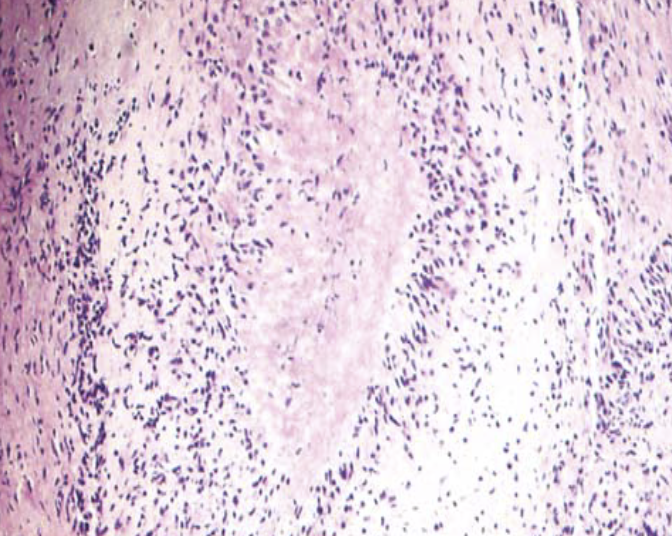

Identify what is seen

A

Rheumatoid nodule ,, subcutaneous mass

identify what is shown

what is your diagnosis

Central area of necrosis surrounded by macrophages & chronic inflammatory infiltrate